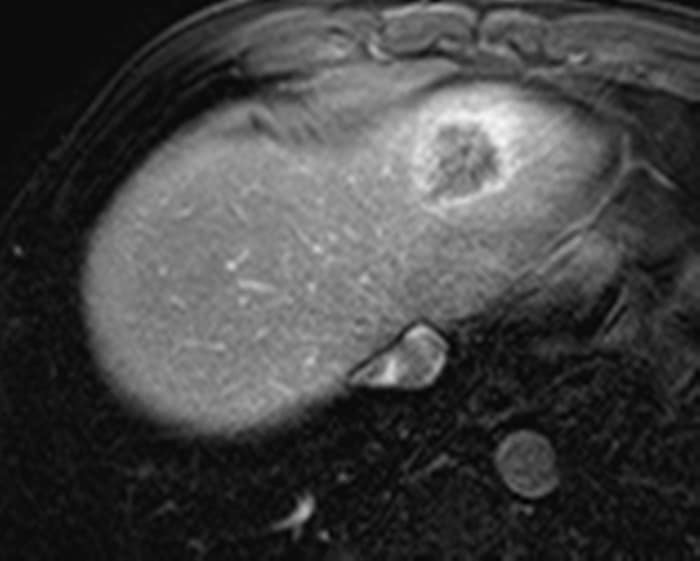

Ung thư đường mật

» Thông tin: Nam giới – 57 tuổi.

» Lâm sàng: Đau bụng.